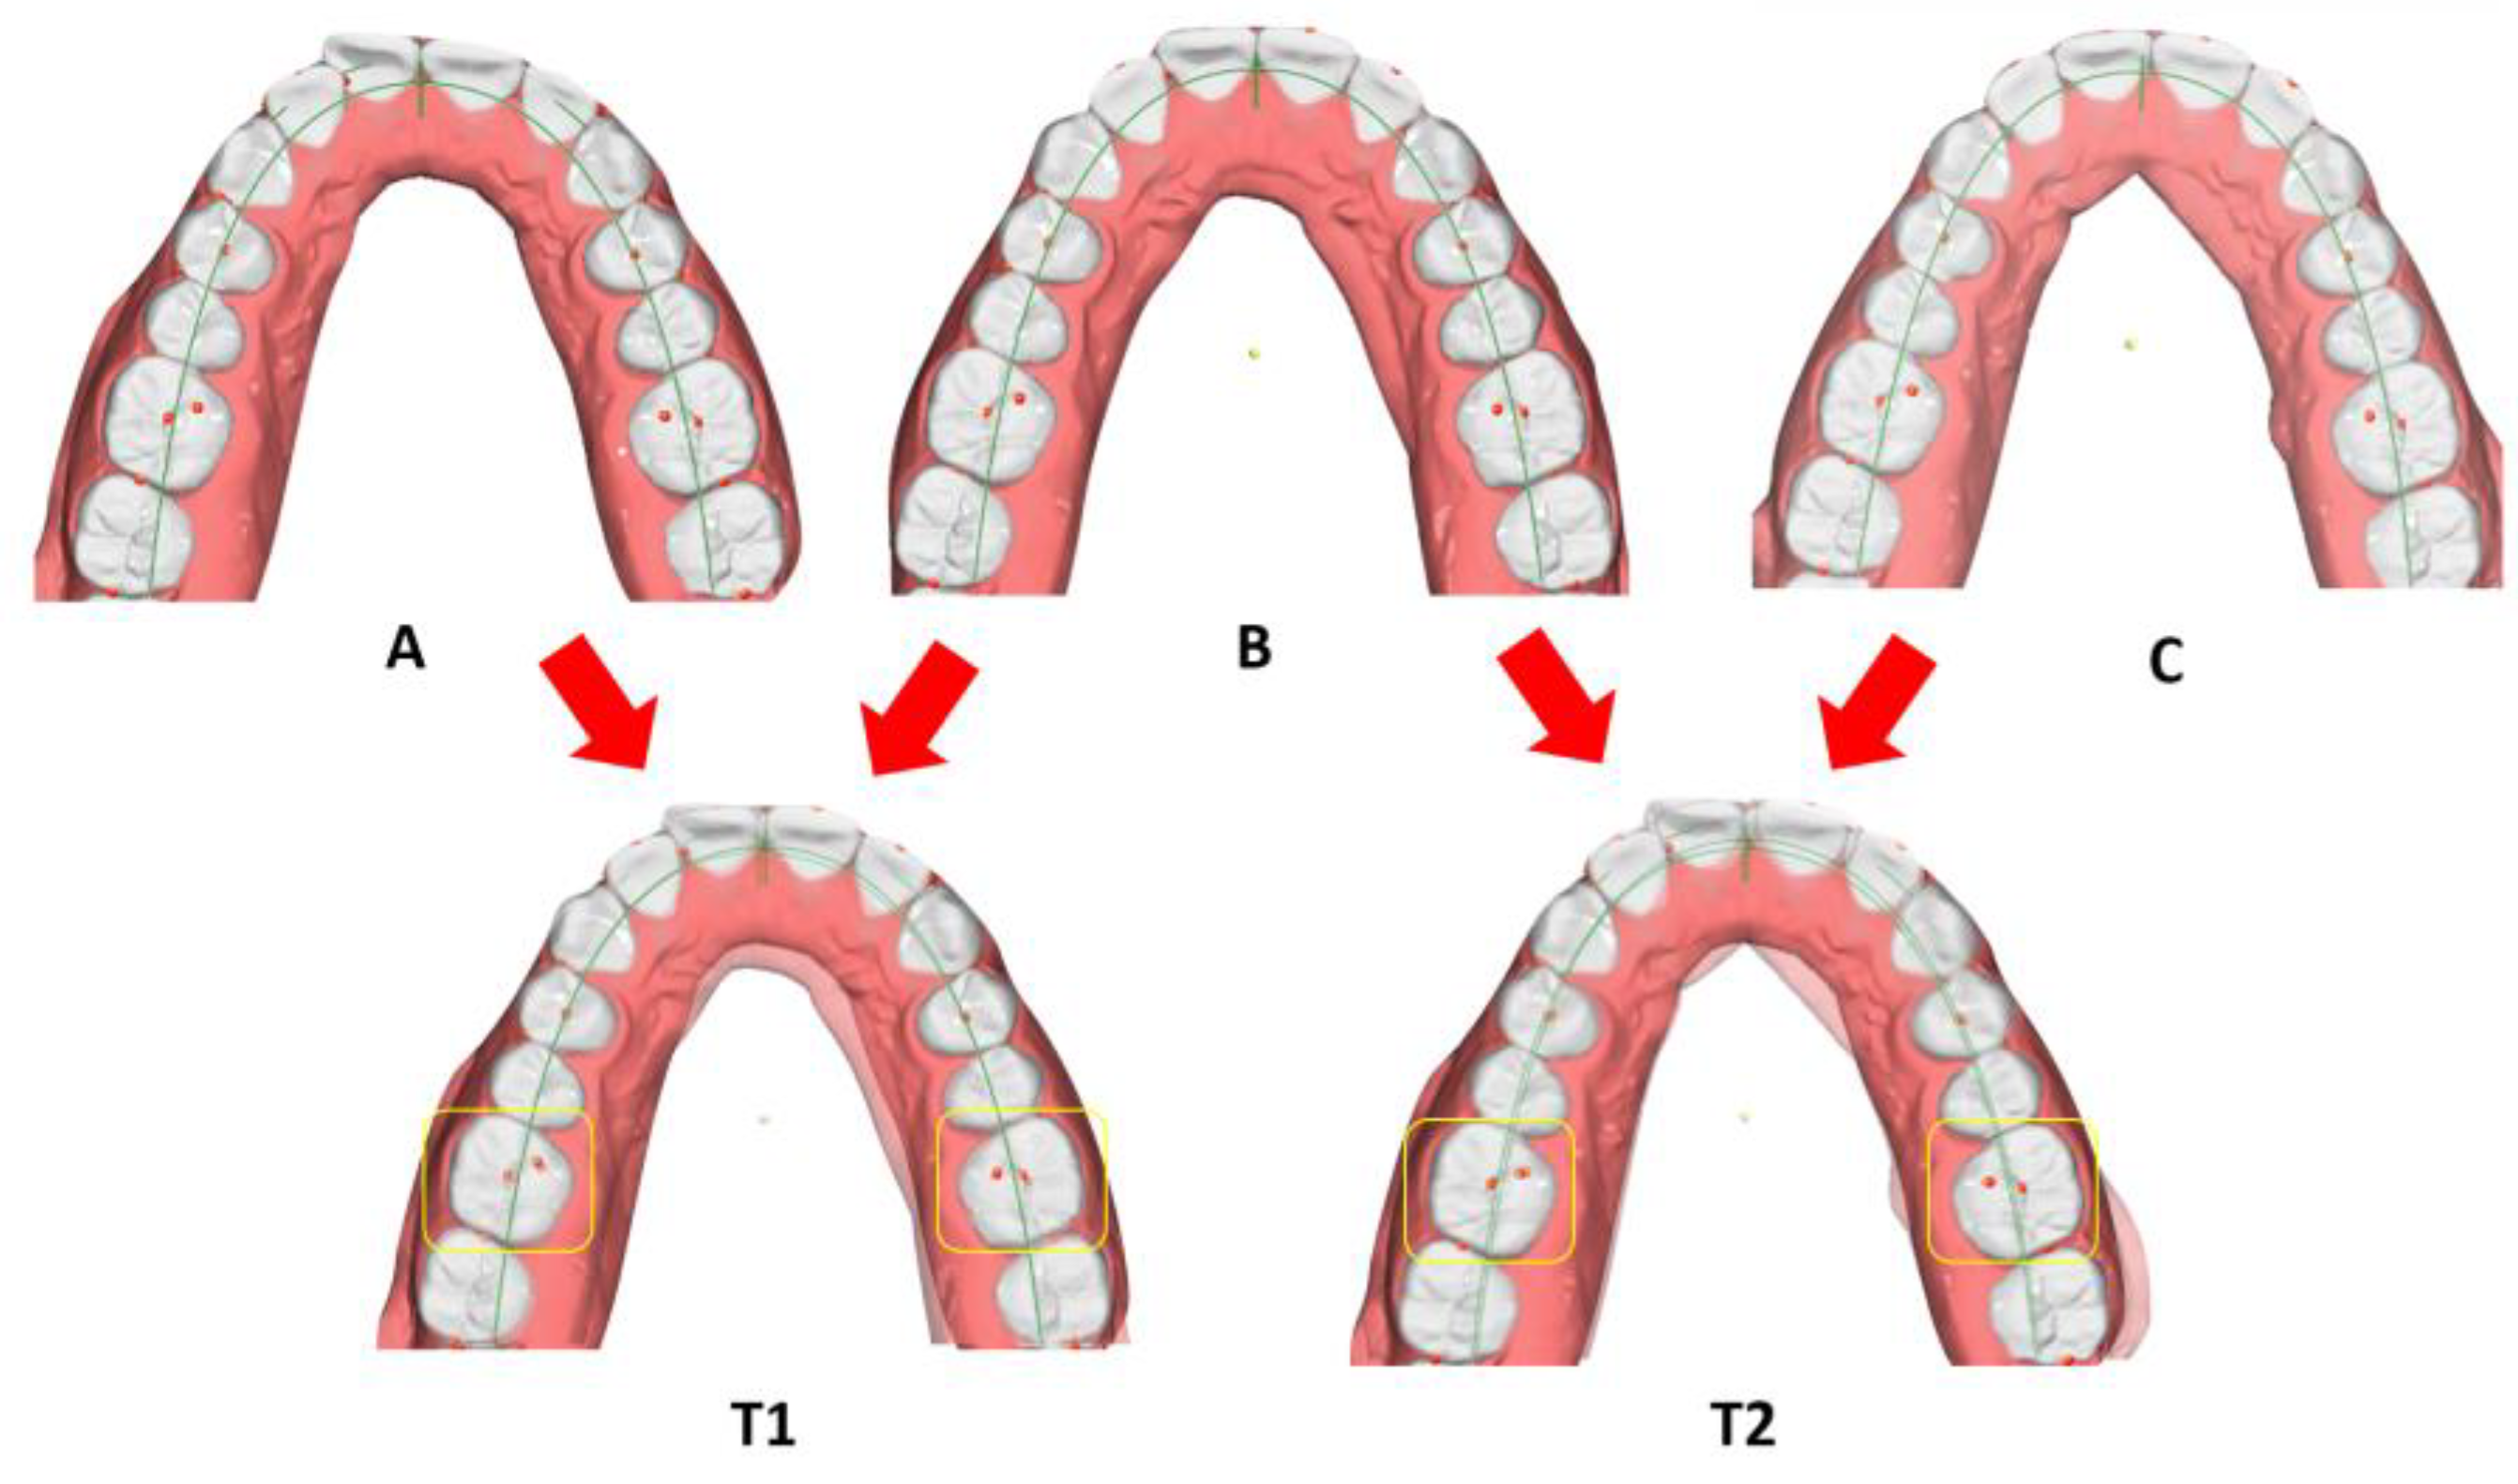

- Prescribed movements (T1): the difference between the pre-treatment and reference model;

- Achieved movements (T2): the difference between the pre-treatment and pre-finishing model (Figure 3) for each movement investigated (inclination, angulation and rotation) and for each tooth (where present, third molars were excluded).

- Inter-canine distance (Ic): measured between the tips of the canine cusps;

- Inter-premolar distance (Ip1): measured between the vestibular cusps on the first premolars;

- Inter-premolar distance (Ip2): measured between the vestibular cusps on the second premolars;

- Inter-molar distance (Im): measured between the mesiovestibular cusps on the first molars (Figure 4).